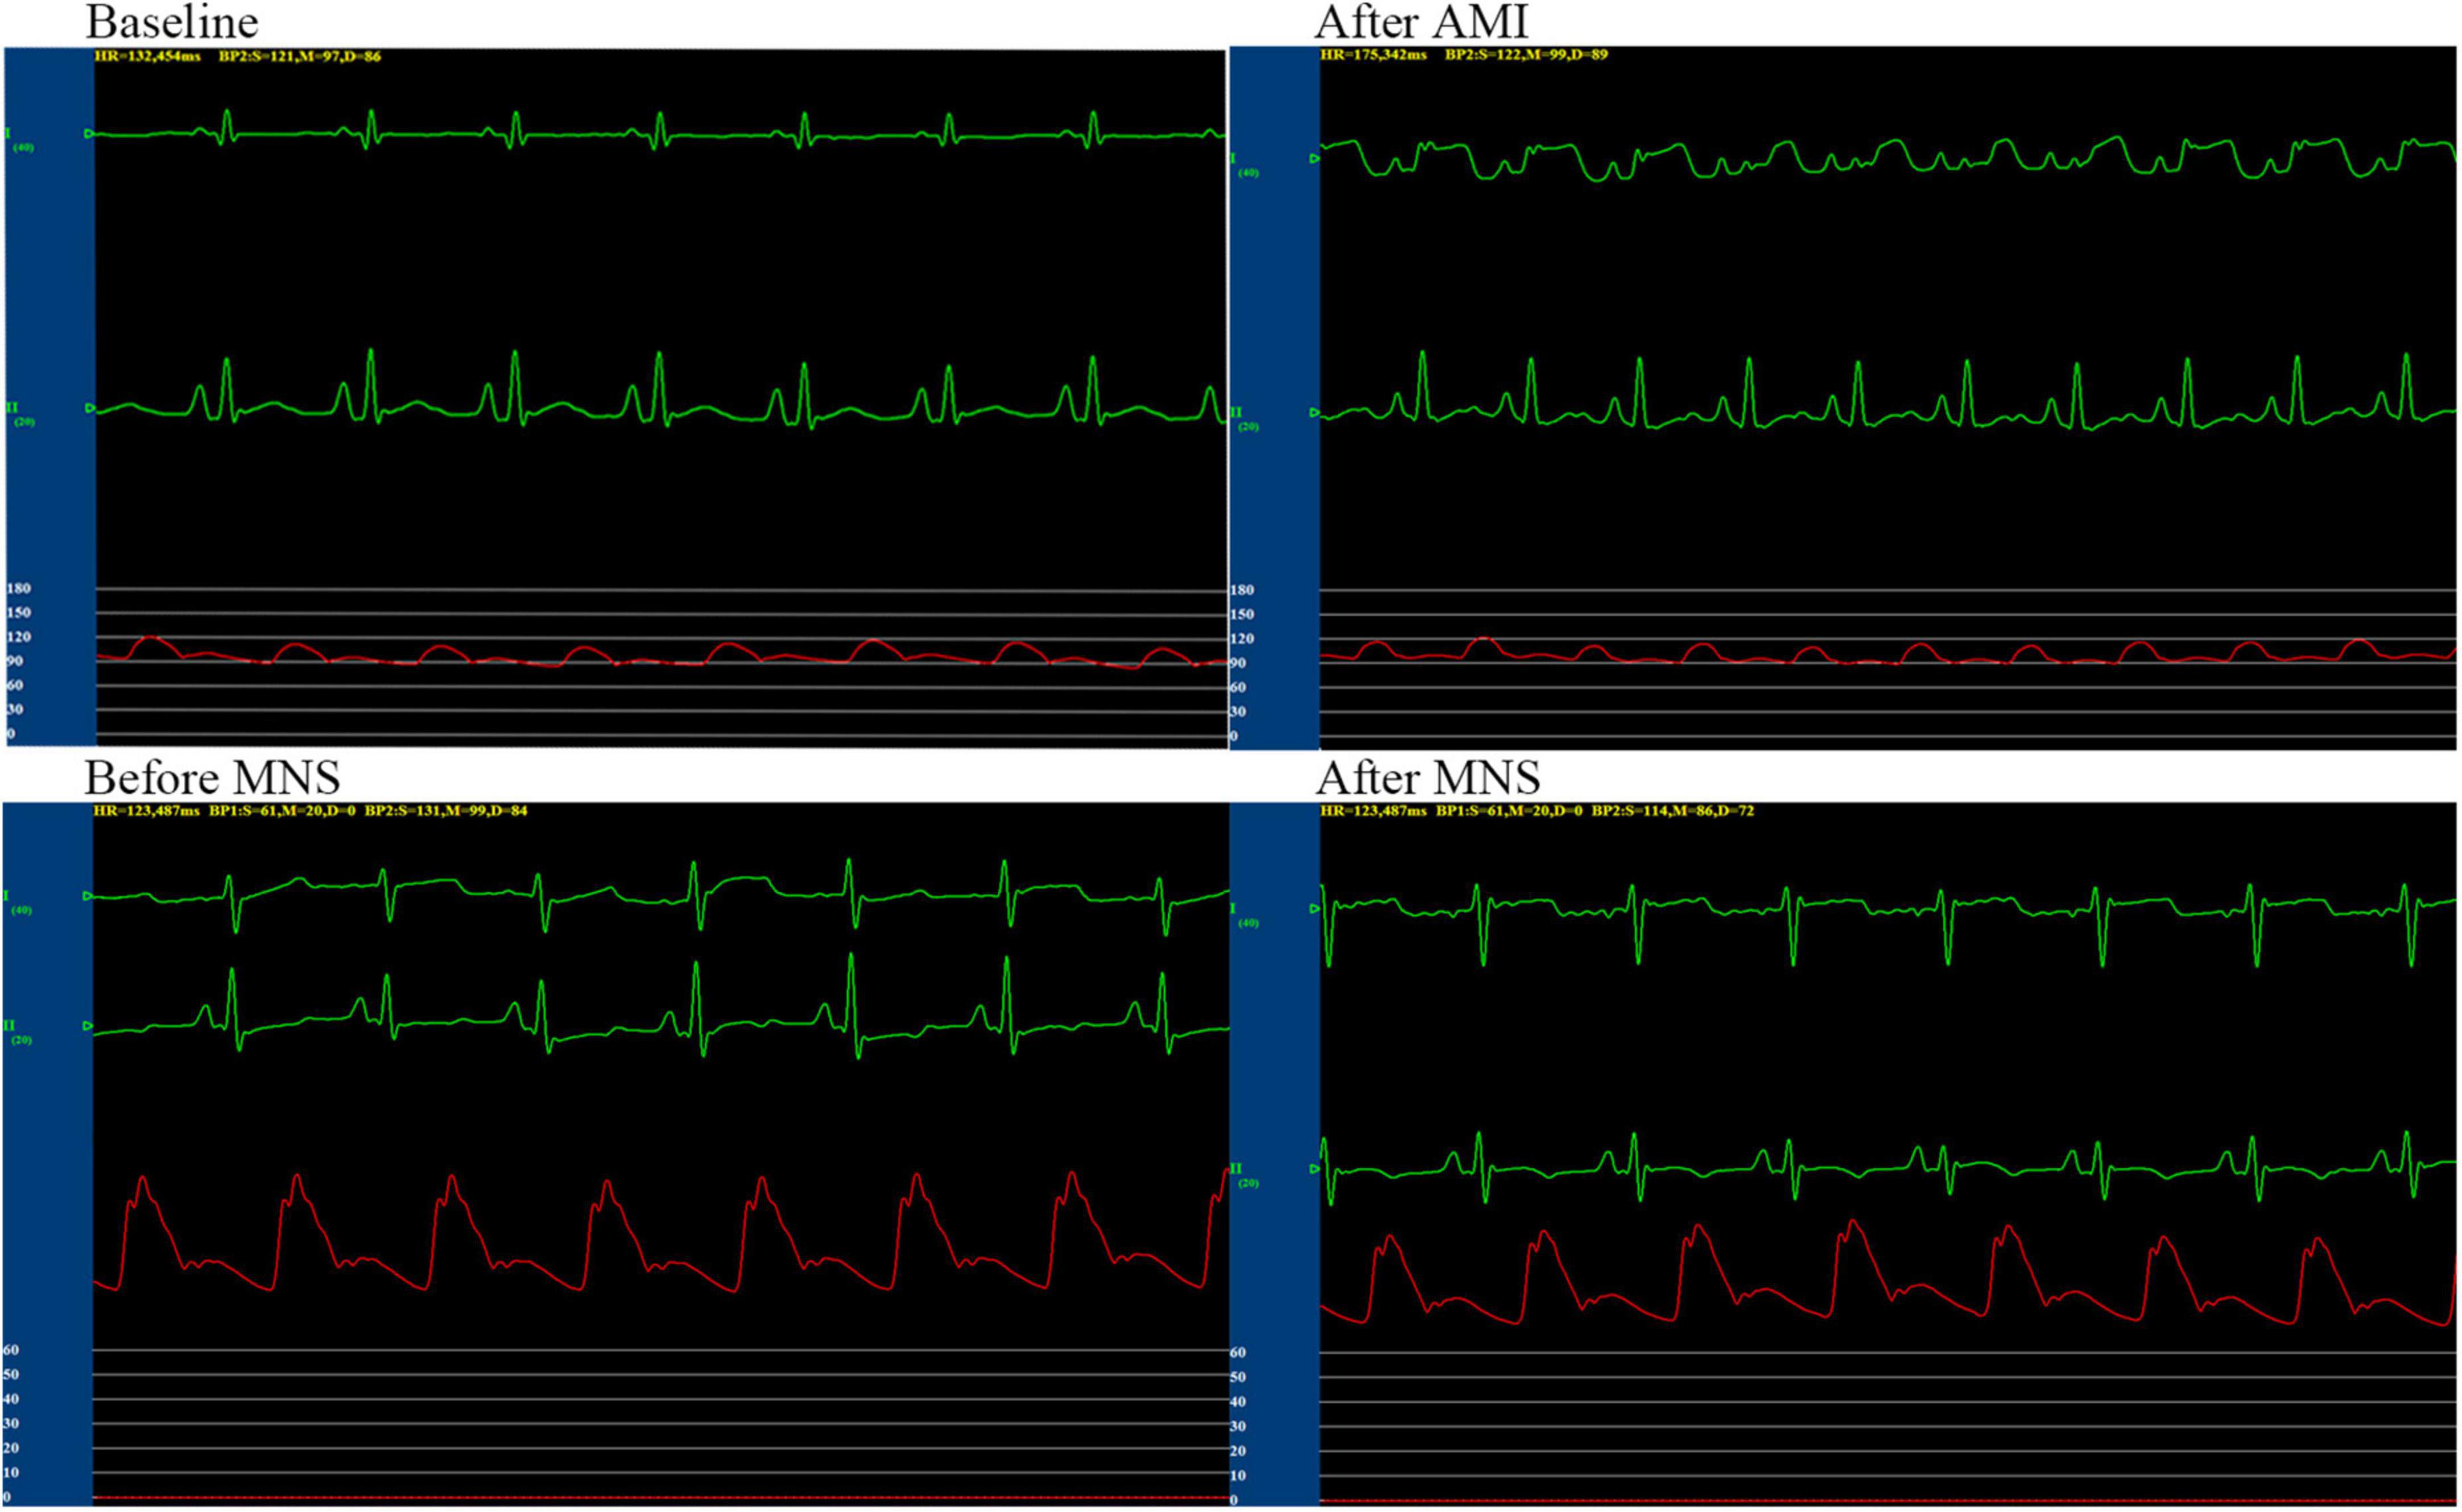

We performed successful experiments on 13 of 15 dogs with acute MI. Two dogs died during the rearing period. After 4 weeks, six dogs and seven dogs were assigned to MNS group 1 and MNS group 2, respectively. During MNS, the heart rate exhibited a decreasing trend in the MNS group 1 and MNS group 2, but this did not contribute to the significant difference. For instance, the heart rate was 125 ± 12 beats/min before MNS and 121 ± 11 beats/min after 30 min of MNS (P > 0.05) in the MNS group 1. The heart rate and blood pressure in the baseline, acute MI, and before and after 30 min of MNS are shown in Table 1 and Figure 4.

Table 1. Heart rate and blood pressure of experimental dogs in baseline, acute myocardial infarction (MI), and after 30 min of median nerve stimulation (MNS).

Figure 4. Representative graphs of blood pressure, heart rate, and electrocardiographic monitoring in the MNS1 group dog during baseline, acute myocardial infarction (MI), and before and after 30 min of MSN. MSN, median nerve stimulation.